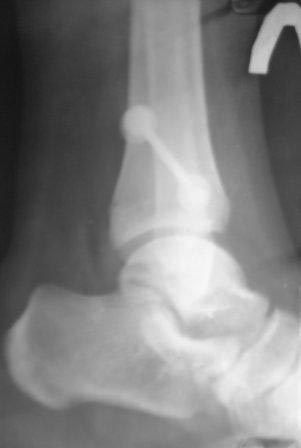

Re: Последствие повреждений дистального межберцового синдесмоза

Нашлись еще снимки, сразу после операции и через год после операции, но снимков до операции не нашли.